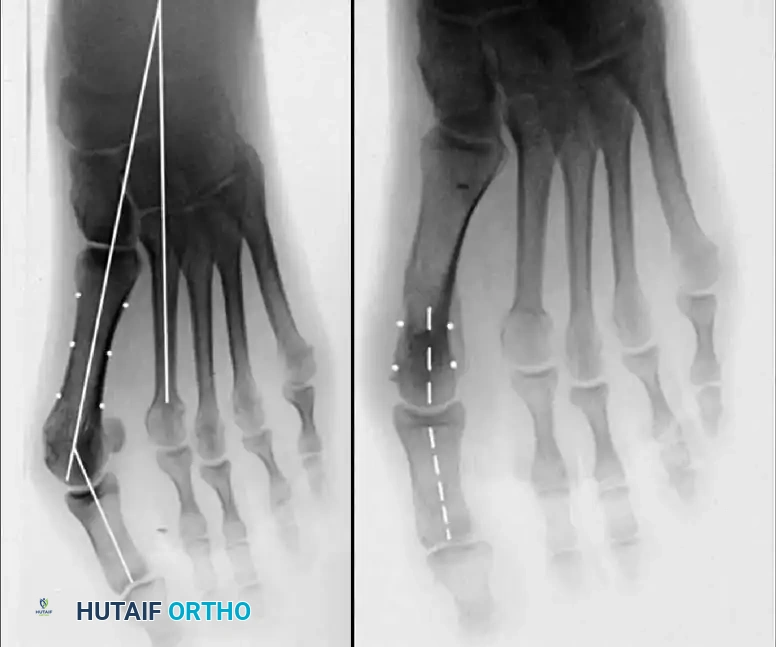

Two other anatomical variants involving the articular surface of the fi rst metatarsophalangeal joint can lead to hallux valgus. In the fi rst variant, the articular surface of the metatarsal head is offset, resembling a scoop of ice cream sitting at an angle on a cone (Fig. 78-6). This has been described as the distal metatarsal articular angle (see Fig. 78-8). In the second, the articular angle of the base of the proximal phalanx in relation to its longitudinal axis is offset. This has been described as the phalangeal articular angle. Although the normal range of these angles is generally considered to be 7 to 10 degrees for the phalangeal articular angle and 10 to 15 degrees for the distal metatarsal articular angle, exact measurements are diffi cult to reproduce because of the variability of radiographic and measurement techniques. Increasing evidence indicates, however, that the failure to correct these two deformities, especially the distal metatarsal articular angle, can cause unsatisfactory results after surgery in some patients. Forceful straightening of the hallux should be avoided if it sacrifi ces tarsalgia. The entire forefoot must be evaluated for these multiple components of hallux valgus before surgical planning is complete and recommendations can be made to the patient. The controversy continues over which deformity is the essential lesion in hallux valgus: metatarsus primus varus or lateral deviation of the great toe. Each is incriminated as the cause of the other. The strongest data probably support lateral deviation of the great toe as the primary deformity in most patients, followed by medial angulation of the fi rst metatarsal, but metatarsus primus varus may be the principal cause in adolescents. Further controversy surrounds the role of footwear as the prime offender in the development of hallux valgus. Most orthopaedic surgeons have seen unilateral hallux valgus when both feet are clinically and radiographically the same structurally except that one foot has a bunion deformity and the other foot is normal. Evidence supports that hallux valgus may be familial, especially when it occurs in adolescents. Although no study of shod and unshod societies has implicated inappropriate footwear as the sole cause of hallux valgus, after genetic factors, binding, unphysiologically designed footwear probably is the major cause in modern societies. Hypermobility of the fi rst ray also has been suggested as a causative factor in the development of hallux valgus and fi rst metatarsal varus, but this is controversial. Coughlin and Shurnas, Myerson and Badekas, King and Toolan, and Faber et al. offer excellent discussions of this problematic area. Finally, certain anatomical and structural abnormalities almost certainly play a causative role in hallux valgus. Pronated fl atfeet, abnormal insertion of the posterior tibial tendon, increased obliquity of the fi rst metatarsomedialcuneiform joint, an abnormally long fi rst ray, incongruous articular surfaces of the fi rst metatarsophalangeal joint, and excessive valgus tilt of the articular surface of the fi rst metatarsal head and proximal phalangeal articular surface may contribute singly or in combination to the deformity and infl uence the recommended treatment. Hypertrophy of the medial eminence has been described as a component of hallux valgus deformity since the earliest reports; however, more recent investigations, including those of Thordarson and Krewer, have found that bony proliferation is not a component of the pathoanatomy of hallux valgus and that the prominence of the medial eminence results from the combination of metatarsus primus varus and medial deviation that uncovers the articular surface. Thordarson and Krewer compared radiographs of 50 feet in patients who had surgery for hallux valgus deformity with radiographs of 50 feet from a control group without hallux valgus deformity and found little difference in the average width of the medial eminence (4.4 mm and 4.1 mm). With more than 130 operations recommended for the treatment of hallux valgus, it is practical to describe only

Fig. 78-6 A, Note valgus orientation of articular surface of fi rst metatarsal head. B, After proximal metatarsal osteotomy on right foot. Sesamoid sling remains dislocated, articular surface of metatarsal head maintains valgus posture, and joint is congruous in valgus. Double osteotomy of fi rst metatarsal (proximally for varus correction and distally for valgus correction of articular surface) and soft-tissue realignment are necessary. Alternatively, arthrodesis of fi rst metatarsophalangeal joint or distal metatarsal osteotomy (chevron) can be performed. Without anatomical reduction of sesamoid sling apparatus, distal metatarsal osteotomy would fail.

Inadequate vascularity or sensibility should be investigated thoroughly before bunion surgery is considered. In addition, the position of the articular surface of the metatarsal head in relation to the longitudinal axis of the fi rst metatarsal should be determined (Fig. 78-8). Standard preoperative radiographs should include standing dorsoplantar and lateral views, a nonstanding lateral oblique view, and axial sesamoid views (Fig. 78-9). The hallux valgus angle and the fi rst-second intermetatarsal angle should fi rst be drawn on the standing dorsoplantar view by bisecting the shafts of the bones (Fig. 78-10), with an awareness of the normal ranges. These angles are most frequently cited as guidelines for treatment decisions, but Donnelly et al. reported that interobserver measurements of the hallux valgus angle varied by approximately 6 degrees and of the intermetatarsal angle by 4 degrees. They cautioned that potential errors in measurement should be considered when these parameters are used to make treatment decisions. The hallux valgus interphalangeus angle and any evidence of degenerative arthritic changes at the fi rst metatarsophalangeal or metatarsocuneiform joints should be documented. Oddities may be present and, if overlooked, may compromise a technically well-done procedure. Mann emphasized that the presence of an os inter-

Fig. 78-8 A, Determination of position of articular surface of metatarsal head in relation to longitudinal axis of fi rst metatarsal. B, Measurement of distal metatarsal articular angle at time of surgery. Markings are at medial and lateral margins of articular surface of fi rst metatarsal head and longitudinal axis of fi rst metatarsal shaft. metatarseum between the bases of the fi rst and second metatarsals might preclude the effectiveness of a soft-tissue procedure alone to provide suffi cient correction of the increased intermetatarsal angle. Likewise, accessory sesamoids and prominent ungual tuberosities at the interphalangeal joint contribute to a painful callus at the tibial side of this joint. An os tibialis externum frequently is associated with excessive hallux valgus interphalangeus. Varus of the fi rst metatarsal might be a signifi cant part of the overall deformity of the foot even with an intermetatarsal angle of less than 10 degrees. Metatarsus varus with a relatively small hallux valgus angle (15 to 20 degrees) may produce signifi cant deformity even though the angles are not excessive. The usefulness of computer-assisted compared with manual measurement of the intermetatarsal angle, hallux valgus angle, and distal metatarsal articular angle is still uncertain. Both methods have closer interobserver and intraobserver correlation in measurement of the intermetatarsal angle and hallux valgus angle than in measurement of the distal metatarsal articular angle. The reliability of either method has such a wide range (5 degrees), however, that measurements of these angles, although useful as a guide, do not provide a completely reliable indication of the magnitude of deformity. Condon et al. suggested that the reliability of the intermetatarsal angle can be improved by careful technique and by making the measurements at least twice and averaging them. Schneider et al. reported two methods of determining angular measurements based on distinctly different reference points: (1) a longitudinal axis of the fi rst metatarsal using middiaphyseal reference points, and (2) a center-head technique using a center head (center of the articular surface) and center base